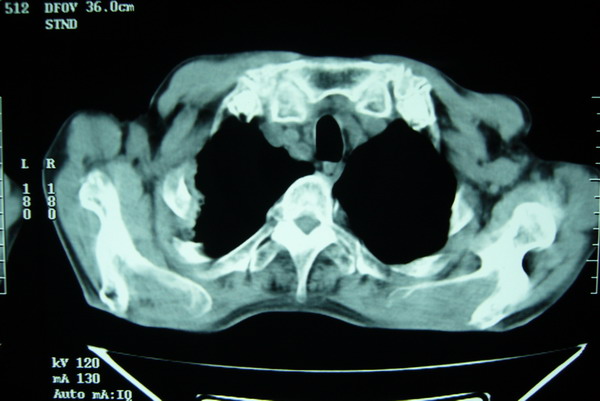

标题: CT15579:男 86岁 咳嗽 咳少量白痰 发热2天 吸烟史60年 [打印本页]

标题: CT15579:男 86岁 咳嗽 咳少量白痰 发热2天 吸烟史60年

右上周围型肺癌,慢支,肺气肿。

右上肺一不规则团块,边缘有分叶和毛刺,纵隔有淋巴结肿大。右肺周围性肺癌首先考虑。